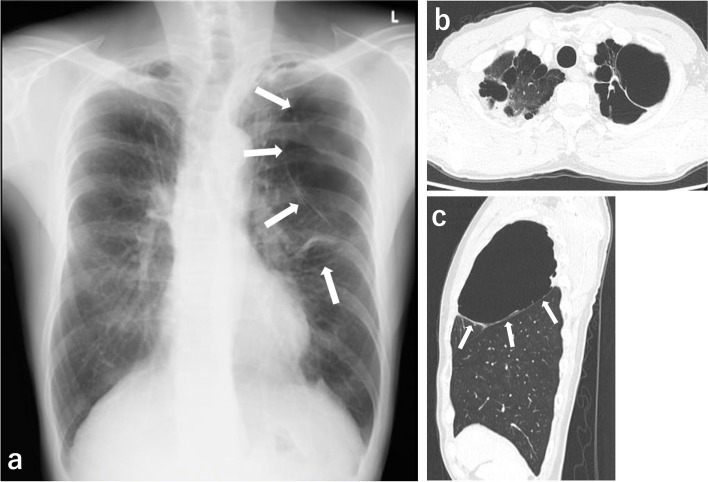

Case presentation: A 52-year-old man with multiple giant bullae underwent video-assisted pulmonary resections, while the ventilation was controlled via a double-lumen bronchial tube. After successful thoracoscopic surgery, an i-gel™ was inserted while the double-lumen tube was still in place, and the double-lumen tube was subsequently removed under deep anesthesia. The i-gel™ was removed without complications after the patient had become able to respond to verbal command.